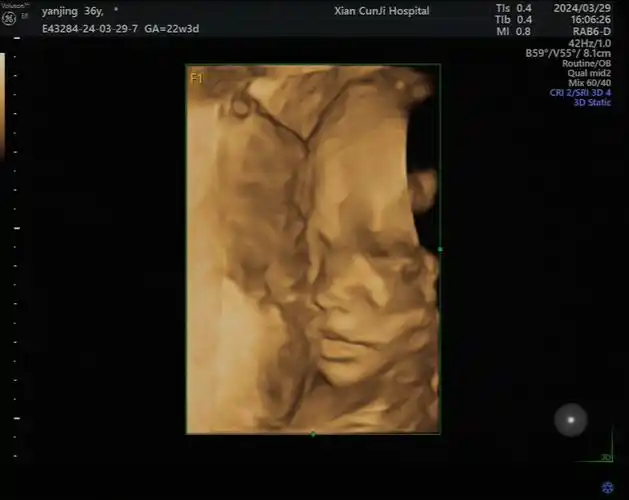

西安存济妇产医院|不远千里,慕名而来,存济妇产见证